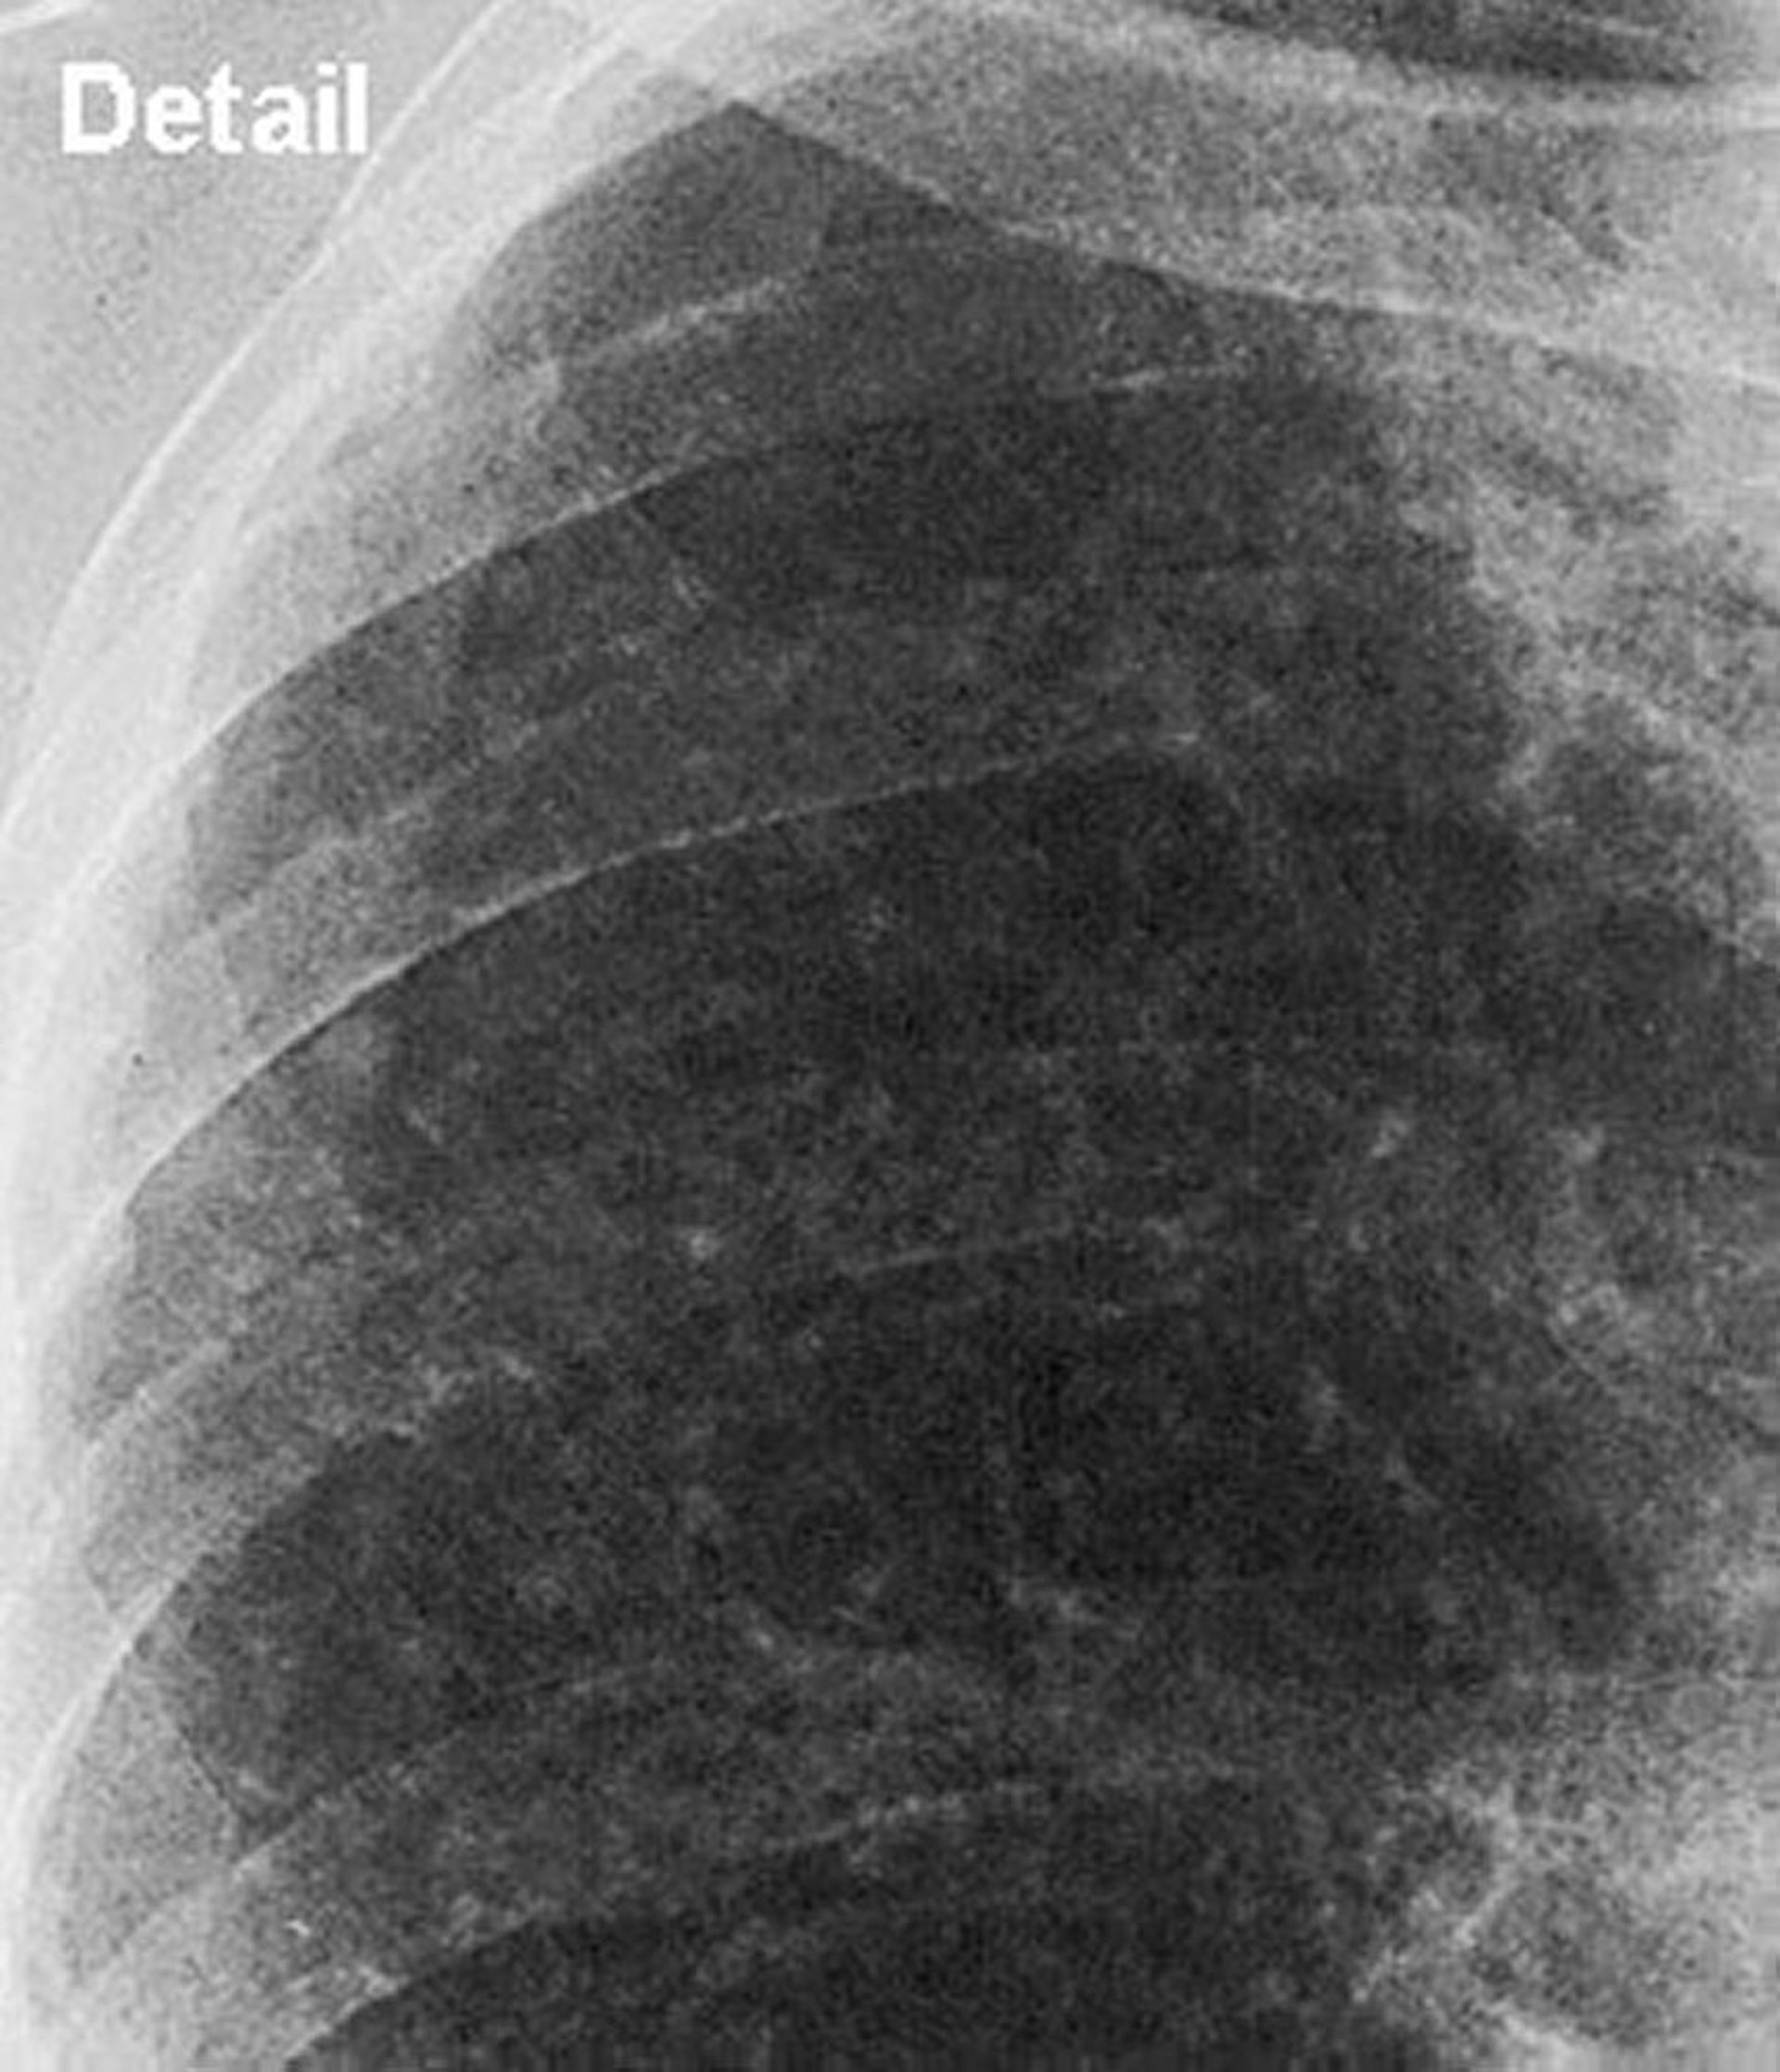

Silicose — simples (campo pulmonar superior)

Incidência em foco do campo pulmonar superior na silicose simples.

Imagem cedida por cortesia de David W. Cugell, MD.